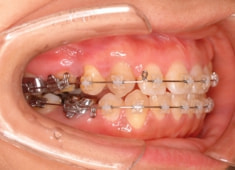

治療開始時

治療開始から約1年2ヶ月後